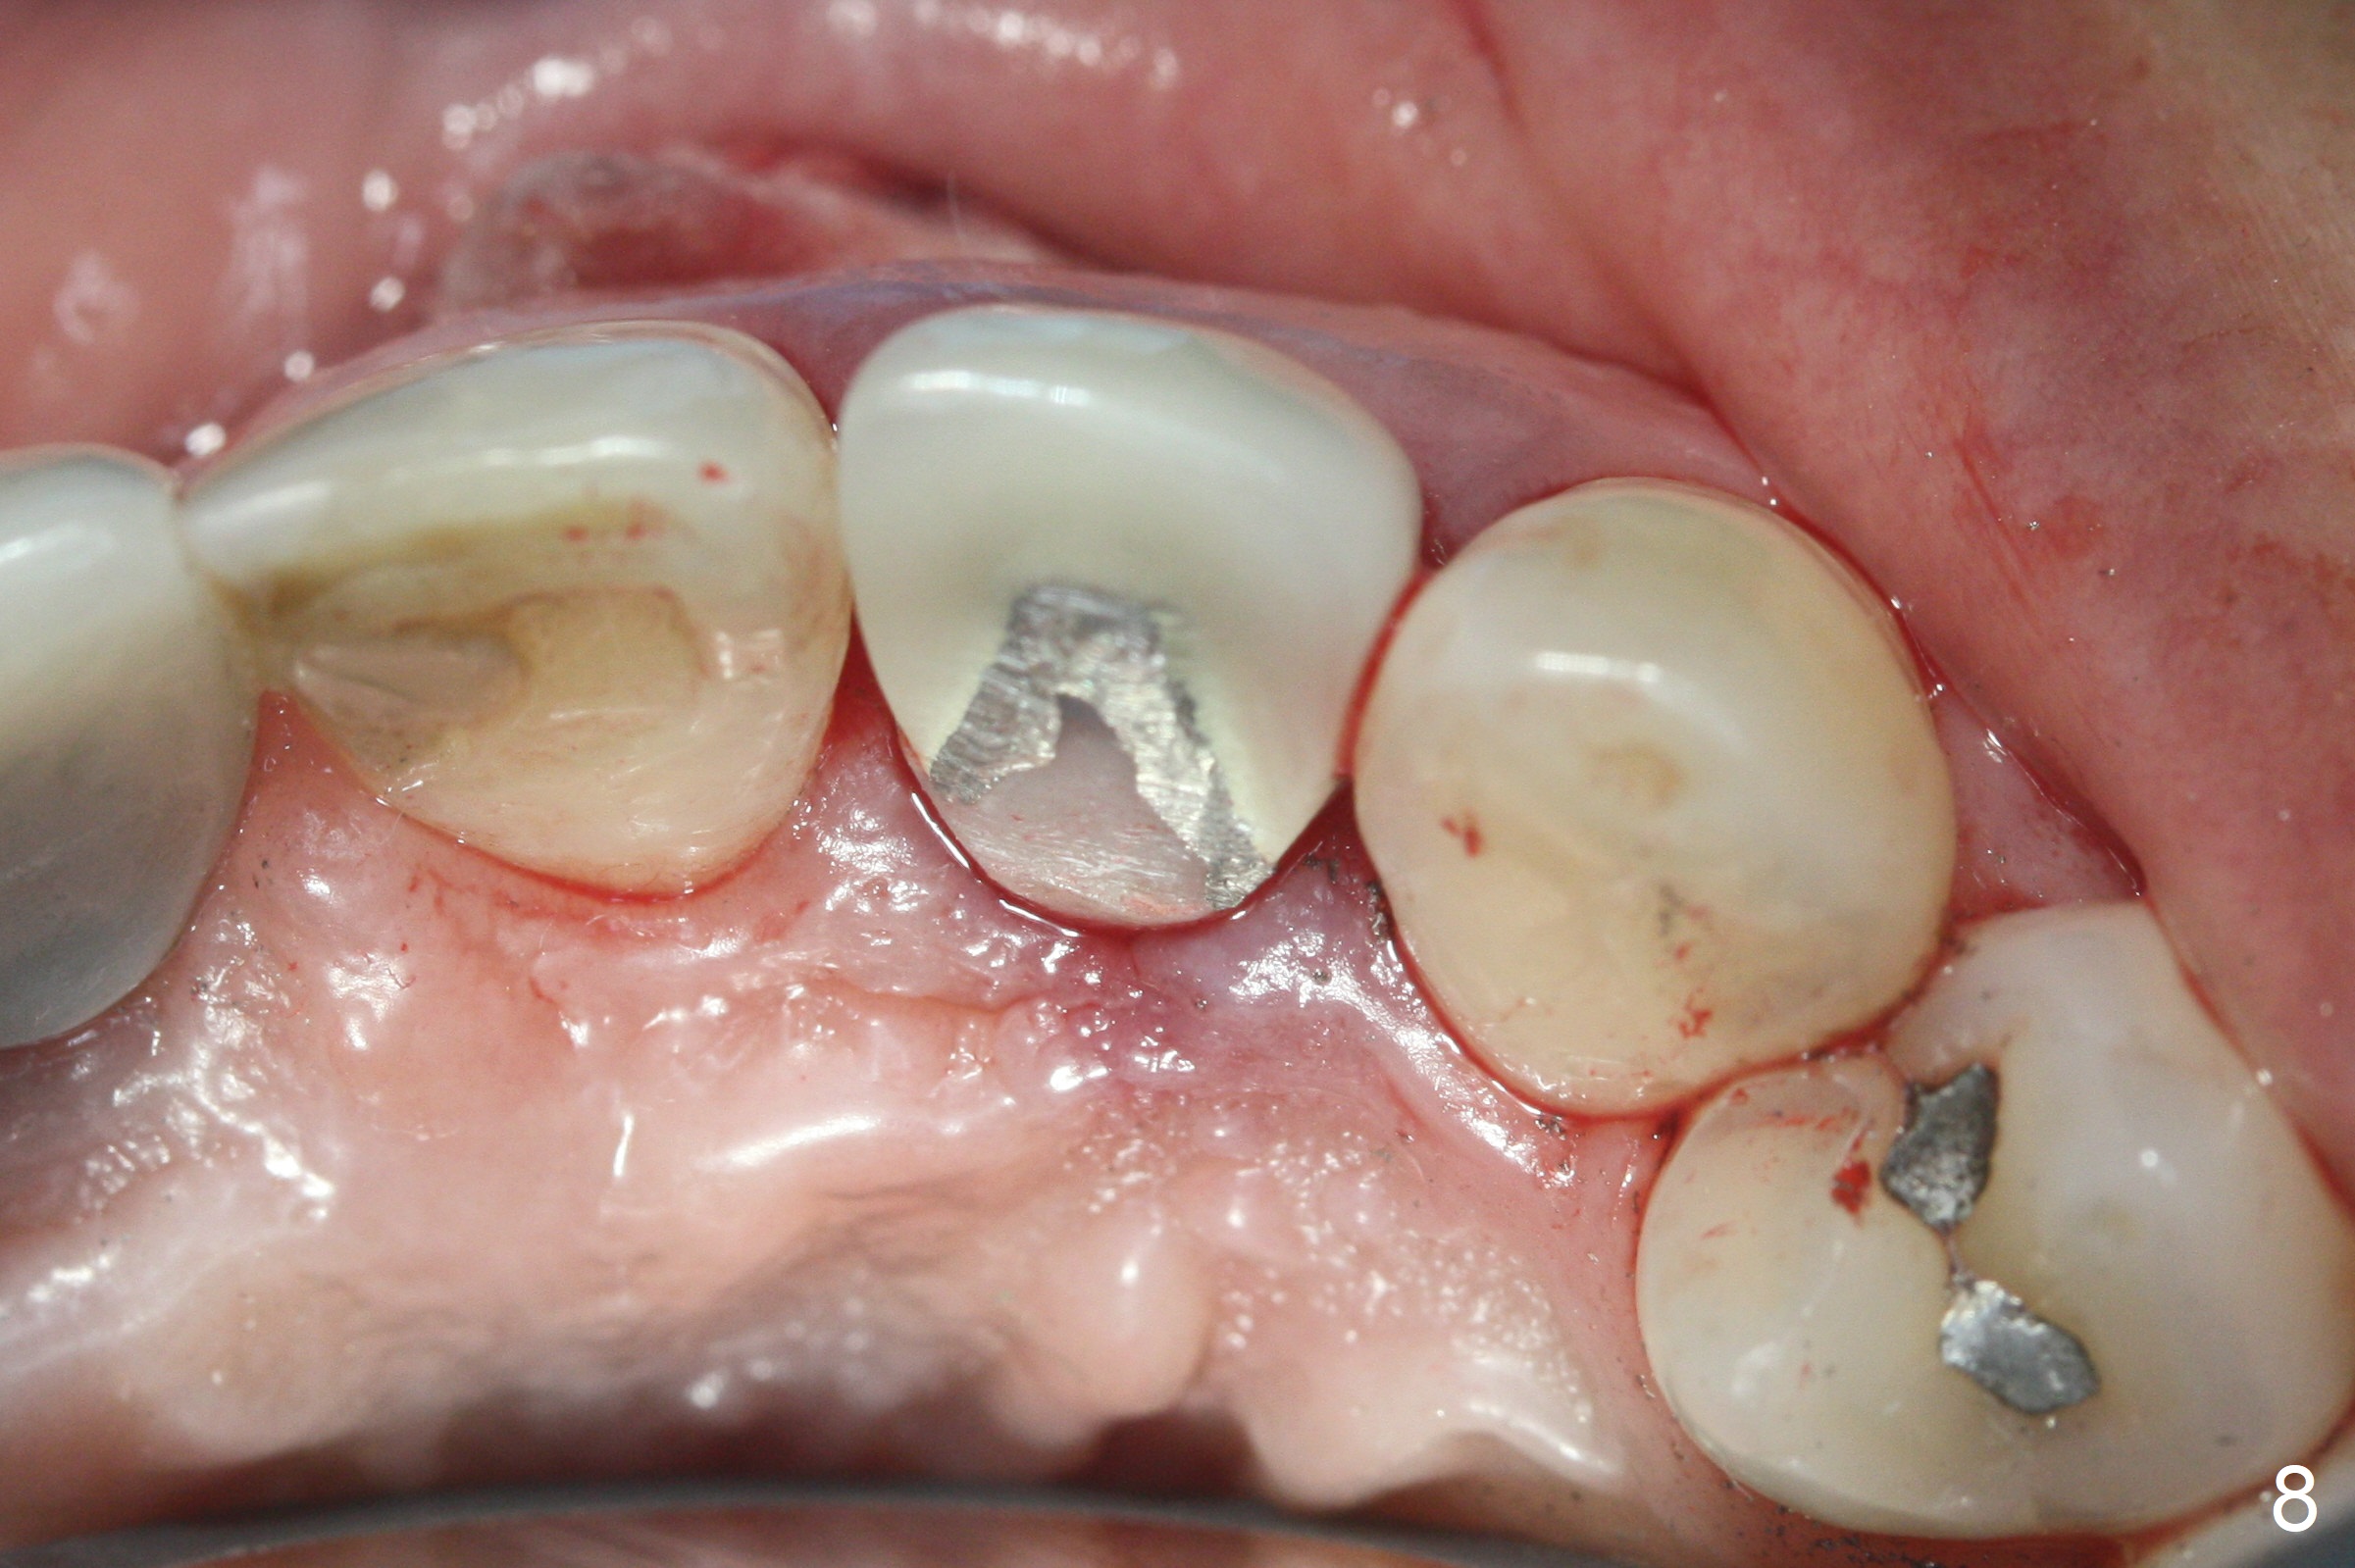

When the patient returns, the crown at #10 has displaced incisally (Fig.1,2 arrow). The initial depth is 15 mm (Fig.3, palatal gingival margin). After a 3.8x12 mm SM implant is placed (Fig.4), allograft is packed in the peri-implant space (*, as compared to Fig.3) and a 3.9x4(3) mm abutment is placed (A). More allograft is placed in the peri-abutment space (Fig.6 *). The existing crown (Fig.4,5 C) is hollowed, relined (R) and used as an immediate provisional (Fig.7-9). The patient is pleased with the appearance of the apically-repositioned provisional (Fig.7 arrow). She returns for impression 3.5 months postop (Fig.10). After change of abutment to 3.9x4(4.5) mm and new provisional, impression is retaken 5 months postop (Fig.11,12). It appears that the implant is palatally placed and a little large for the site (Fig.11 (B: buccal); Fig.12 (^: thin layer of the palatal plate)). If an angled abutment were used, a screw-retained crown might have been feasible. Due to the new provisional, the gingiva looks healthy when a permanent crown is cemented (Fig.13).